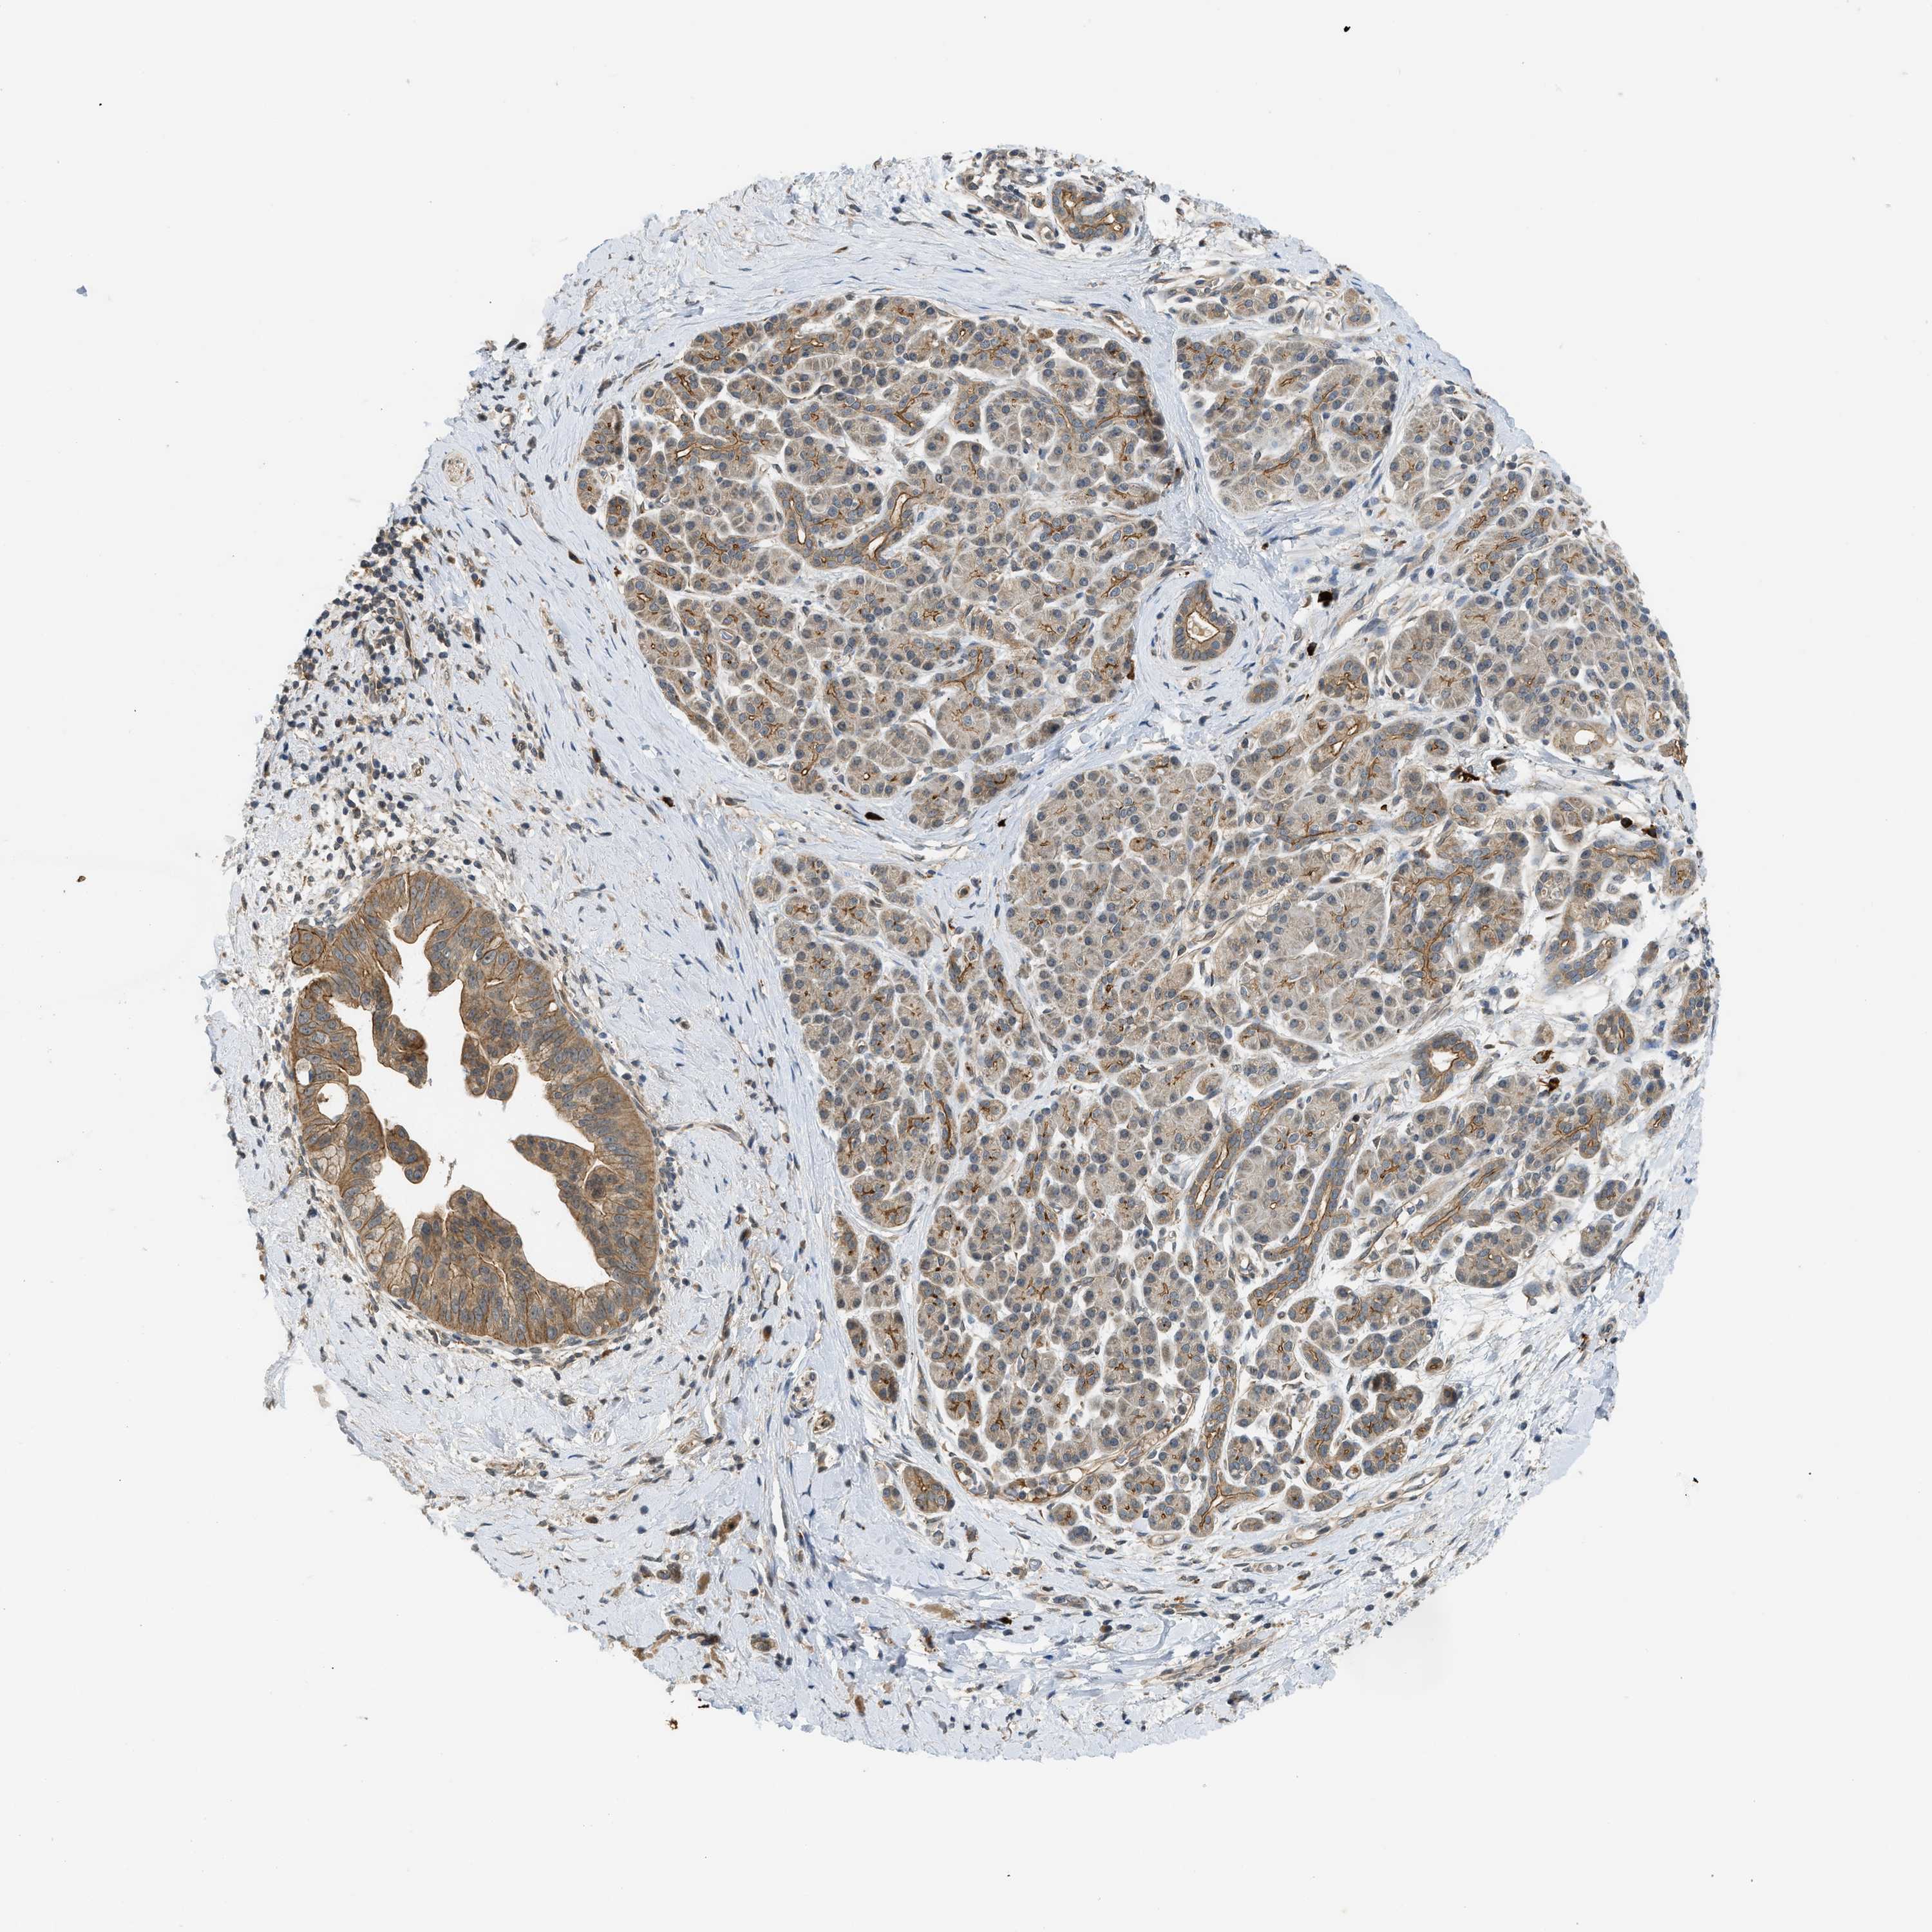

PANCREATIC CANCER - Protein expressioni

A mouse-over function shows sample information and annotation data. Click on an image to view it in a full screen mode. Samples can be filtered based on level of antibody staining by selecting one or several of the following categories: high, medium, low and not detected. The assay and annotation is described here.

Note that samples used for immunohistochemistry by the Human Protein Atlas do not correspond to samples in the TCGA dataset.

Antibody stainingi

Antibody staining in the annotated cell types in the current human tissue is reported as not detected, low, medium, or high, based on conventional immunohistochemistry profiling in selected tissues. This score is based on the combination of the staining intensity and fraction of stained cells.

Each image is clickable and will lead to virtual microscopy that enables deeper exploration of all samples and also displays staining intensity scores, fraction scores and subcellular localization as well as patient and tissue information for each sample.

Antibody HPA024291

Antibody CAB018652

Staining

High

Medium

Low

Not detected

Intensity

Strong

Moderate

Weak

Negative

Quantity

>75%

75%-25%

<25%

None

Location

Nuclear

Cytoplasmic/membranous

Cytoplasmic/membranous,nuclear

Adenocarcinoma, NOS